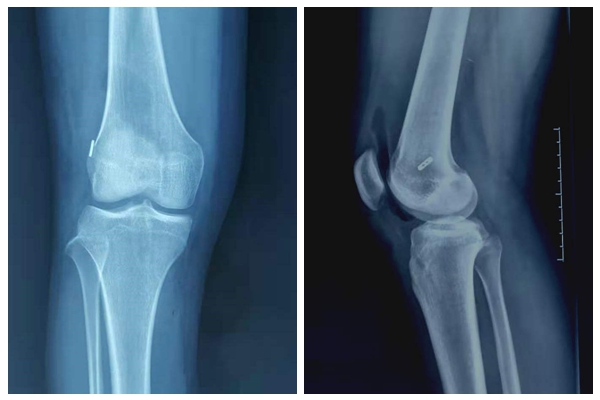

李寬新主任、張衡博士進(jìn)行了詳細(xì)的術(shù)前設(shè)計(jì),在膝關(guān)節(jié)磁共振上測(cè)量前交叉韌帶脛骨止點(diǎn)大小,在B超上評(píng)估半腱肌腱、股薄肌腱的粗細(xì),確定股骨、脛骨隧道的最佳解剖位置。2020年12月22日李寬新主任、張衡博士共同為患者實(shí)施關(guān)節(jié)鏡下自體Hamstring肌腱前交叉韌帶個(gè)性化解剖重建手術(shù)。術(shù)中應(yīng)用自主研發(fā)的關(guān)節(jié)鏡下測(cè)量器測(cè)量前交叉韌帶脛骨止點(diǎn)面積,按照張衡博士改良的韌帶大小計(jì)算公式計(jì)算出需要移植的Hamstring肌腱的直徑,并采用國(guó)際流行的Three portal 和AAMP法建立股骨隧道技術(shù)實(shí)施肌腱移植。手術(shù)僅4個(gè)Mini小切口,微創(chuàng)、美觀。術(shù)后膝關(guān)節(jié)X線示:前交叉韌帶隧道方向、膝關(guān)節(jié)解剖關(guān)系良好。